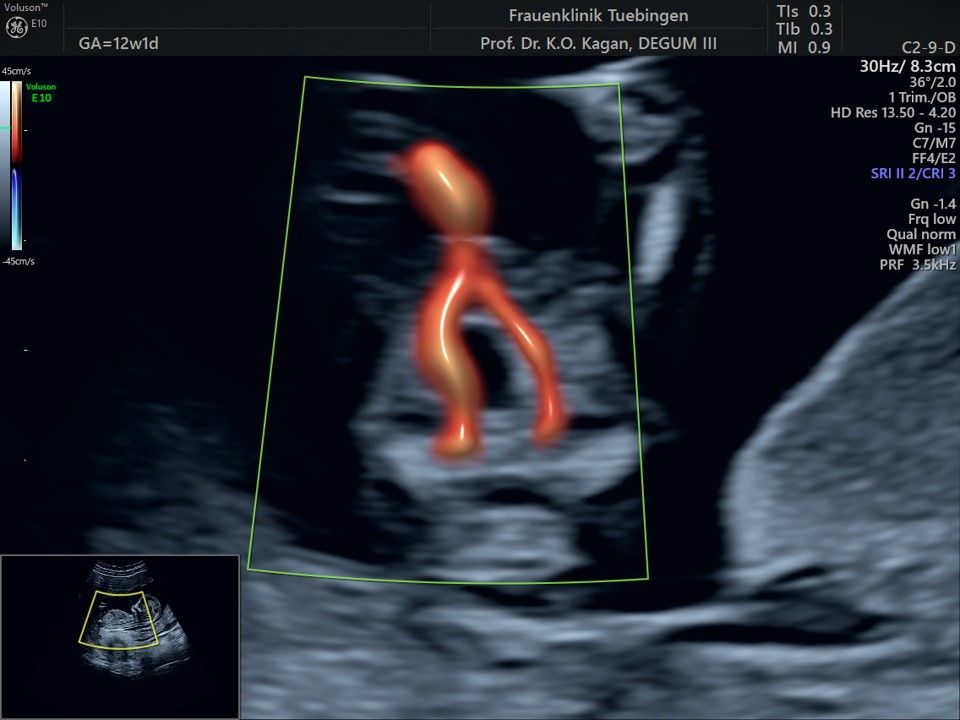

Im Rahmen des Ersttrimester-Screenings untersuchen wir die Organe des Feten mittels Ultraschall. Dabei machen wir auch gerne ein Bild für Sie.

Obwohl der Fet zu diesem Zeitpunkt erst zwischen 5 und 8cm groß ist, lassen sich bereits etwa die Hälfte aller schwerwiegenden Fehlbildungen erkennen bzw. ausschließen. Sollten wir eine Auffälligkeit sehen, werden wir mit Ihnen den Befund und das weitere Vorgehen ausführlich besprechen.

Fetale Anatomie